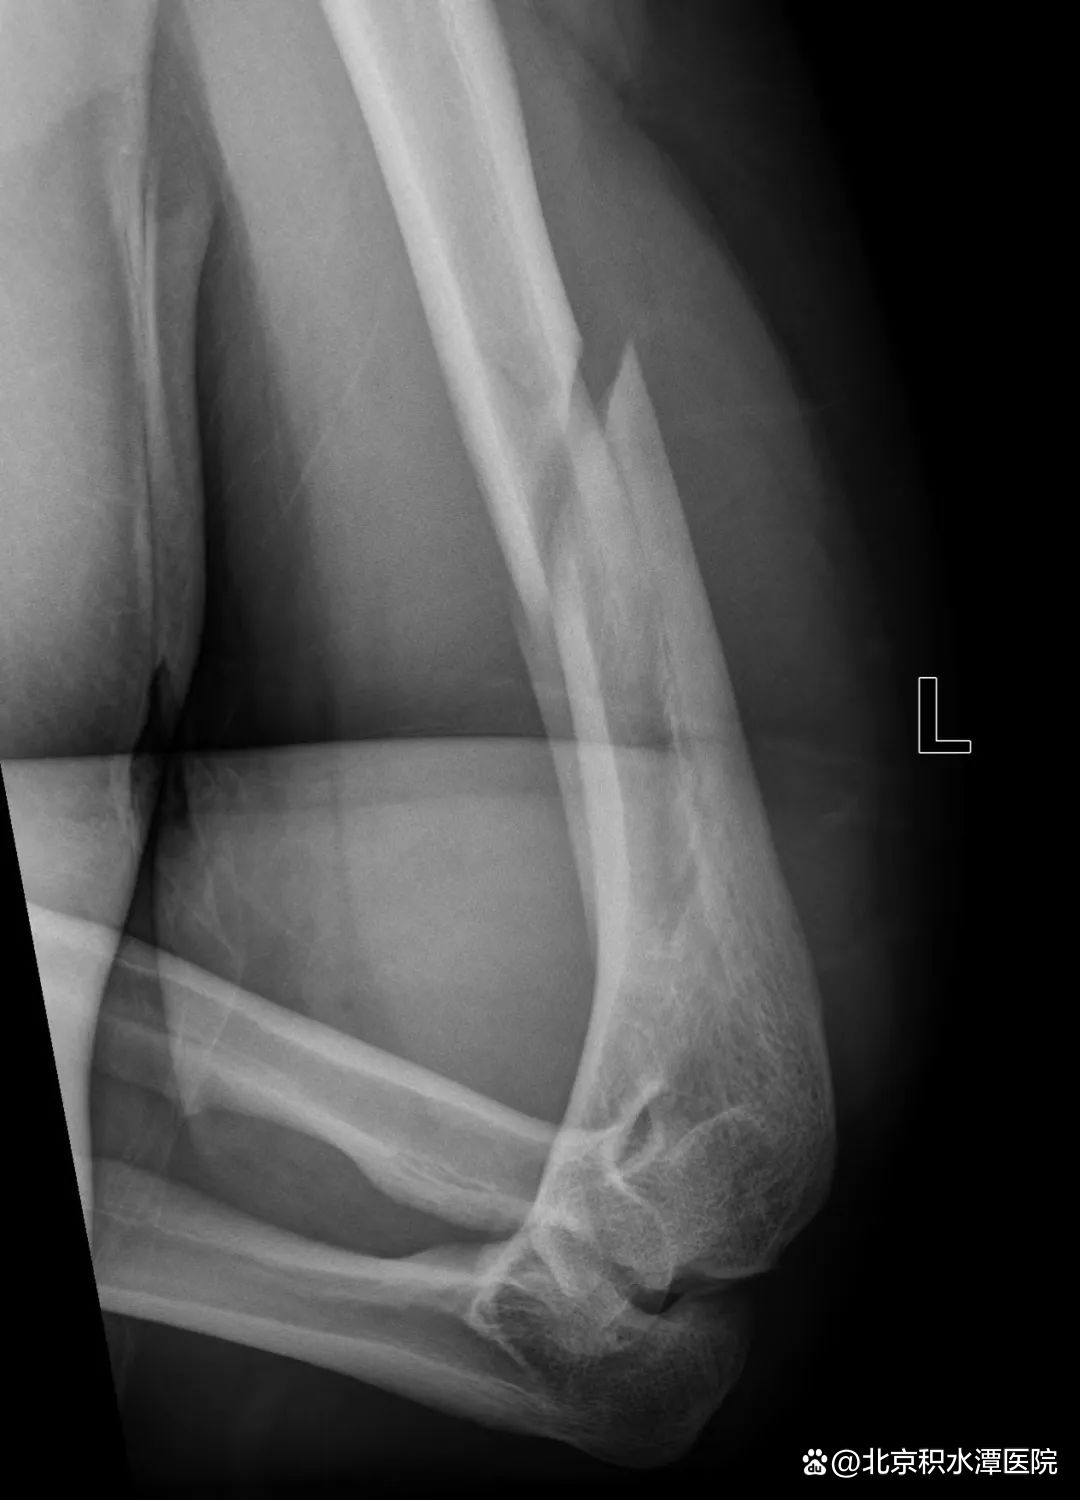

图|扳手腕导致的肱骨干骨折

由于存在共同的受伤机制,扳手腕导致的肱骨干骨折表现极为相似。这类骨折几乎都是肱骨远端三分之一螺旋形骨折,半数伴有蝶形骨折片,在AO/OTA分型中分别为12-A1型和12-B1型,可伴有桡神经损伤。